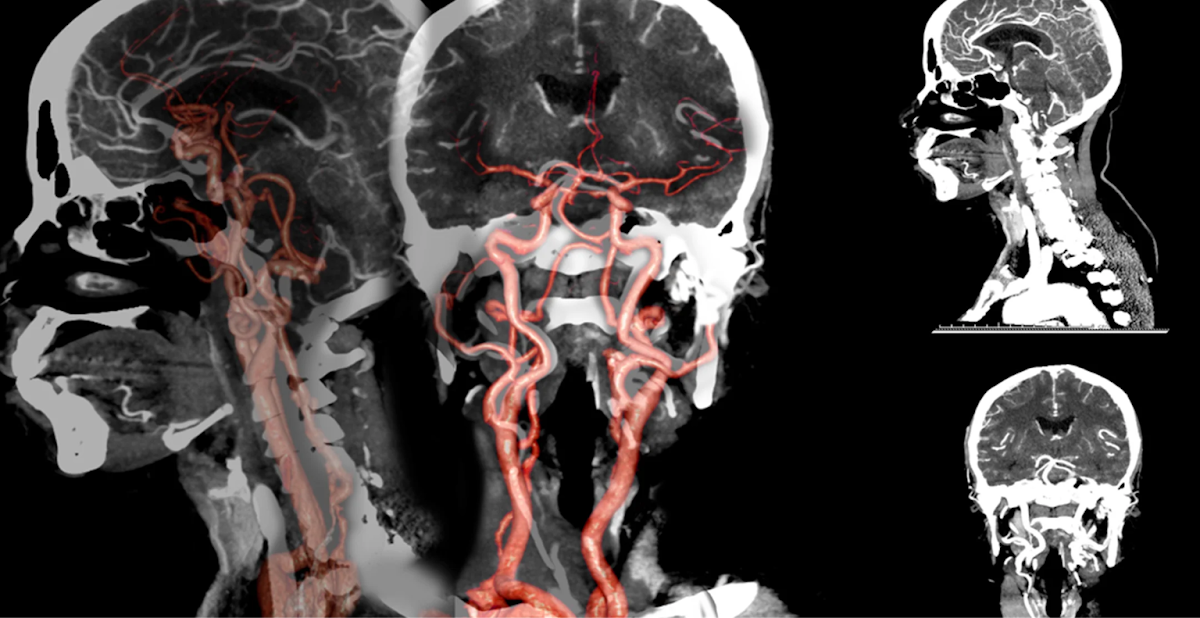

КТ-ангіографія — це сучасний метод обстеження судин, який дозволяє побачити їх стан без катетерів, розрізів і госпіталізації. Дослідження триває кілька хвилин і дає лікарю детальну 3D-картину артерій та вен у будь-якій ділянці тіла. Саме тому цей метод дедалі частіше замінює класичну інвазивну ангіографію в діагностичних цілях.

КТ-ангіографія є неінвазивним методом візуалізації судин, що дозволяє детально оцінити їх стан без необхідності хірургічного втручання. Основним принципом цього методу є болюсне контрастування, яке забезпечує чітке зображення судинної системи. Це досягається шляхом введення контрастної речовини, яка підсилює видимість судин на знімках, отриманих за допомогою комп’ютерної томографії.

Основою КТ-ангіографії є болюсне введення контрастної речовини у вену. Контраст «підсвічує» судини, і комп’ютерна томографія фіксує їх у момент максимального наповнення кров’ю. У результаті отримують чіткі пошарові зображення, які можна переглядати у різних площинах та реконструкціях.

КТ-ангіографія дозволяє виявити аневризми — патологічні розширення судин, що можуть становити загрозу розриву. Чим раніше виявлена аневризма, тим більше шансів запобігти небезпечним ускладненням. Метод також точно визначає стенози — звуження артерій, які порушують кровотік і можуть призводити до інсульту або інфаркту.

Метод також застосовується для виявлення вроджених судинних мальформацій, тромбозів, тромбоемболії легеневої артерії та порушень мозкового кровообігу. У невідкладних ситуаціях КТ-ангіографія дозволяє швидко прийняти клінічне рішення, що може врятувати життя.